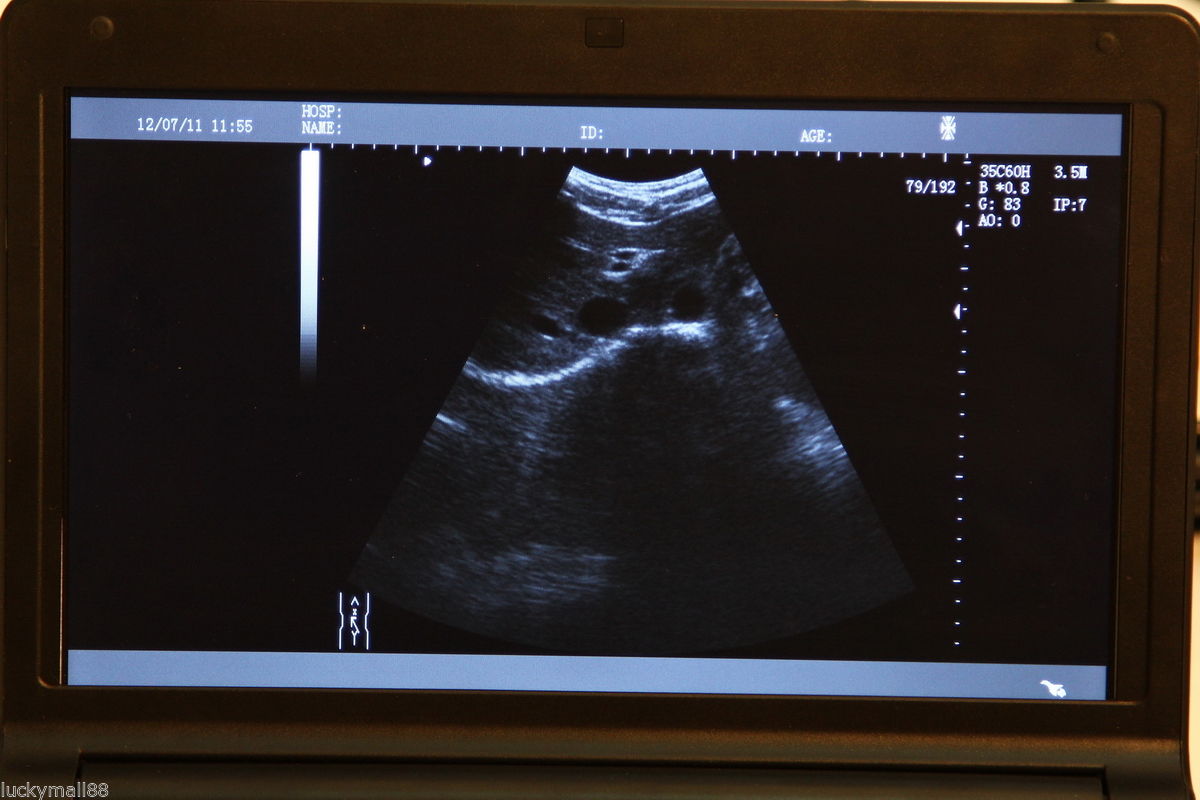

DIAGNOSTIC ULTRASOUND MACHINES FOR SALE

Ultrasound Scanner machine Rectal Probe 3D Laptop Machine Digital Veterinary AA 190891879431

Sale price$ 1,866.31

Regular price$ 2,275.99

Ultrasound Scanner Veterinary Pregnancy US-96 with 3.5 MHz Convex Probe.

Sale price$ 1,758.07

Regular price$ 2,143.99

DIAGNOSTIC ULTRASOUND MACHINES FOR SALE

Ultrasound Scanner Veterinary Pregnancy US-96 with 7.5 MHz Rectal Probe.

Sale price$ 1,844.18

Regular price$ 2,249.00